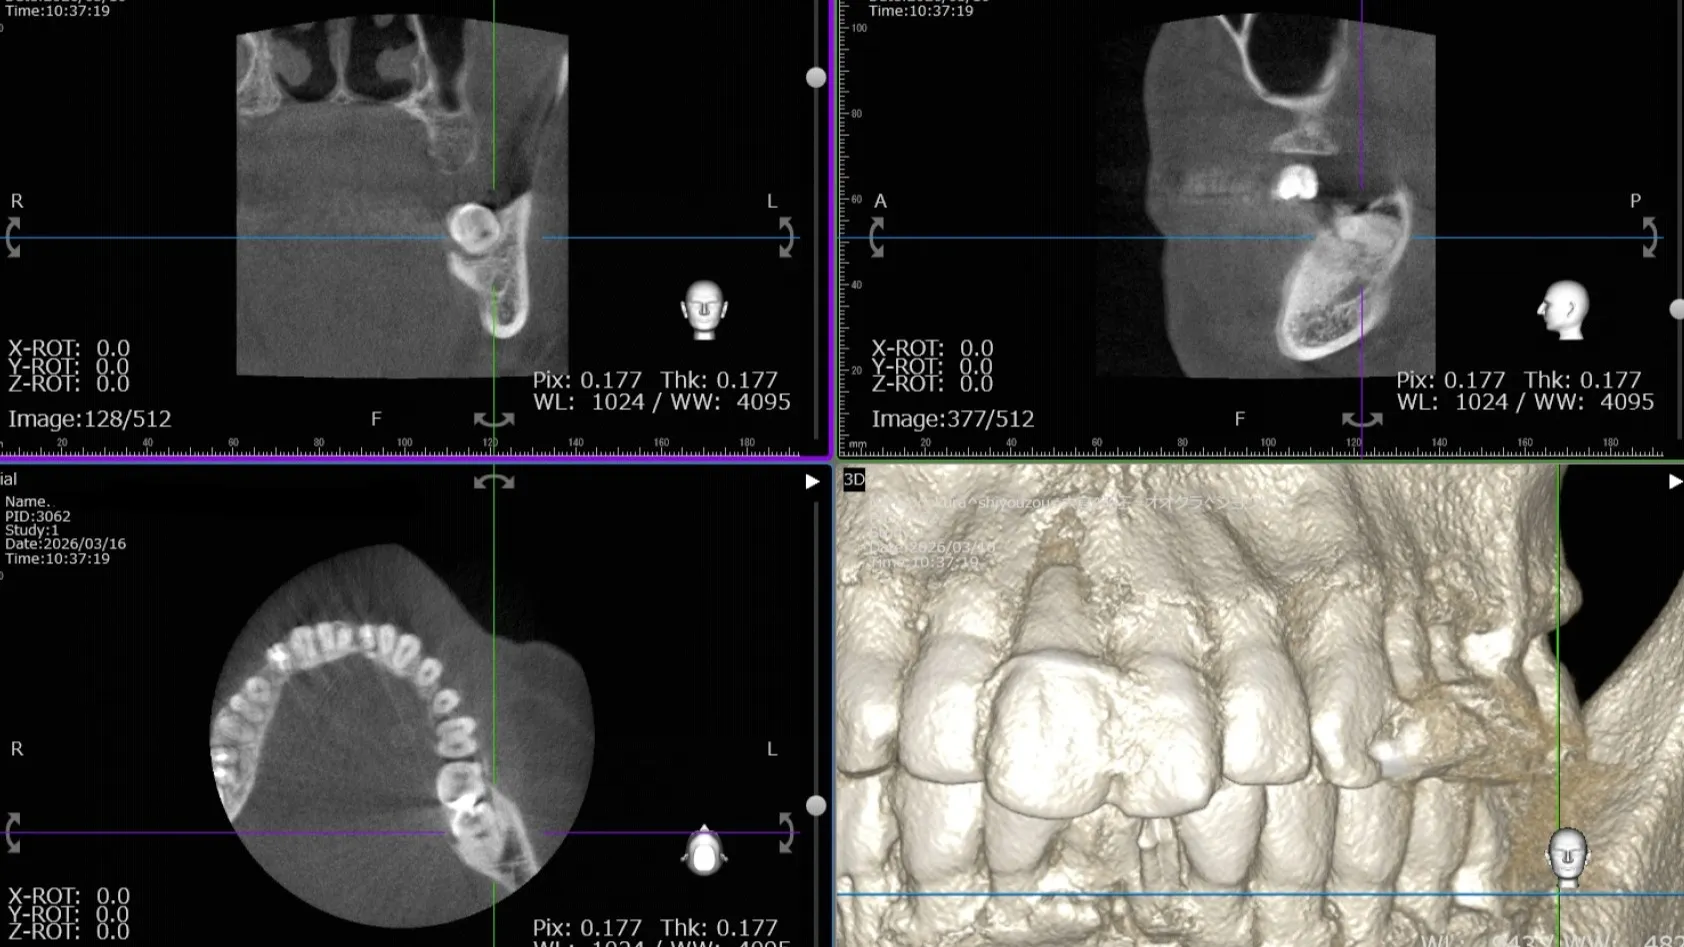

今回は目視で親知らずに虫歯が確認できるほかにレントゲン撮影やCT撮影で歯の方向や不良補綴物をしっかり確認🤩

また埋もれている親知らずは、太い神経を近くに通っている可能性があるため、太い神経(下歯槽神経)との距離をしっかり測定して抜歯が安全に行えることや、歯の根の状態や生え方を確認して抜歯の時にどの方向に力を加えるかを事前に確認します🫡